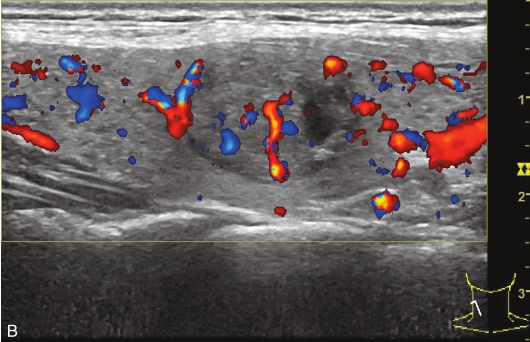

女性,56岁,体检超声发现甲状腺结节1周,无不适。甲状腺功能正常,实验室检查:FT3 3.76pmol/L,FT4 11.68pmol/L,TSH 2.8414μIU/ml。手术病理提示结节性甲状腺肿。

甲状腺形态基本正常,甲状腺实质回声稍增粗,分布尚均匀,甲状腺包膜尚光滑。甲状腺两叶内见多发结节,较大者位于左叶上极,呈类椭圆形,边界清楚,形态规则,纵横比<1,内部回声均匀,未见钙化,后方回声稍增强。CDFI显示左叶较大结节边缘可见丰富的条状血流信号,内部可见条状、点状血流信号,见图1-3-7。

图1-3-7 结节性甲状腺肿常规超声表现

A.常规超声图像;B.CDFI超声图像

甲状腺左叶上极较大结节增强早期呈稍高增强,自结节外周向中央灌注,增强晚期呈等增强,结节内部可见不均匀低增强区,见图1-3-8、ER1-3-4。

图1-3-8 结节性甲状腺肿超声造影图像